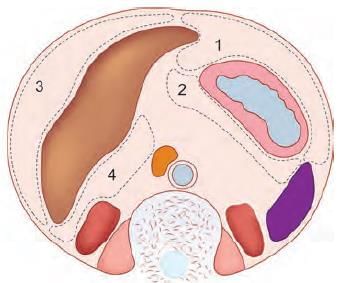

Which of the following is most common site for intraperitoneal abscess in relation to liver? (NEET-PG 2022)

The anatomical structure at the arrow marked location is a defect in: (NEET-PG 2023)